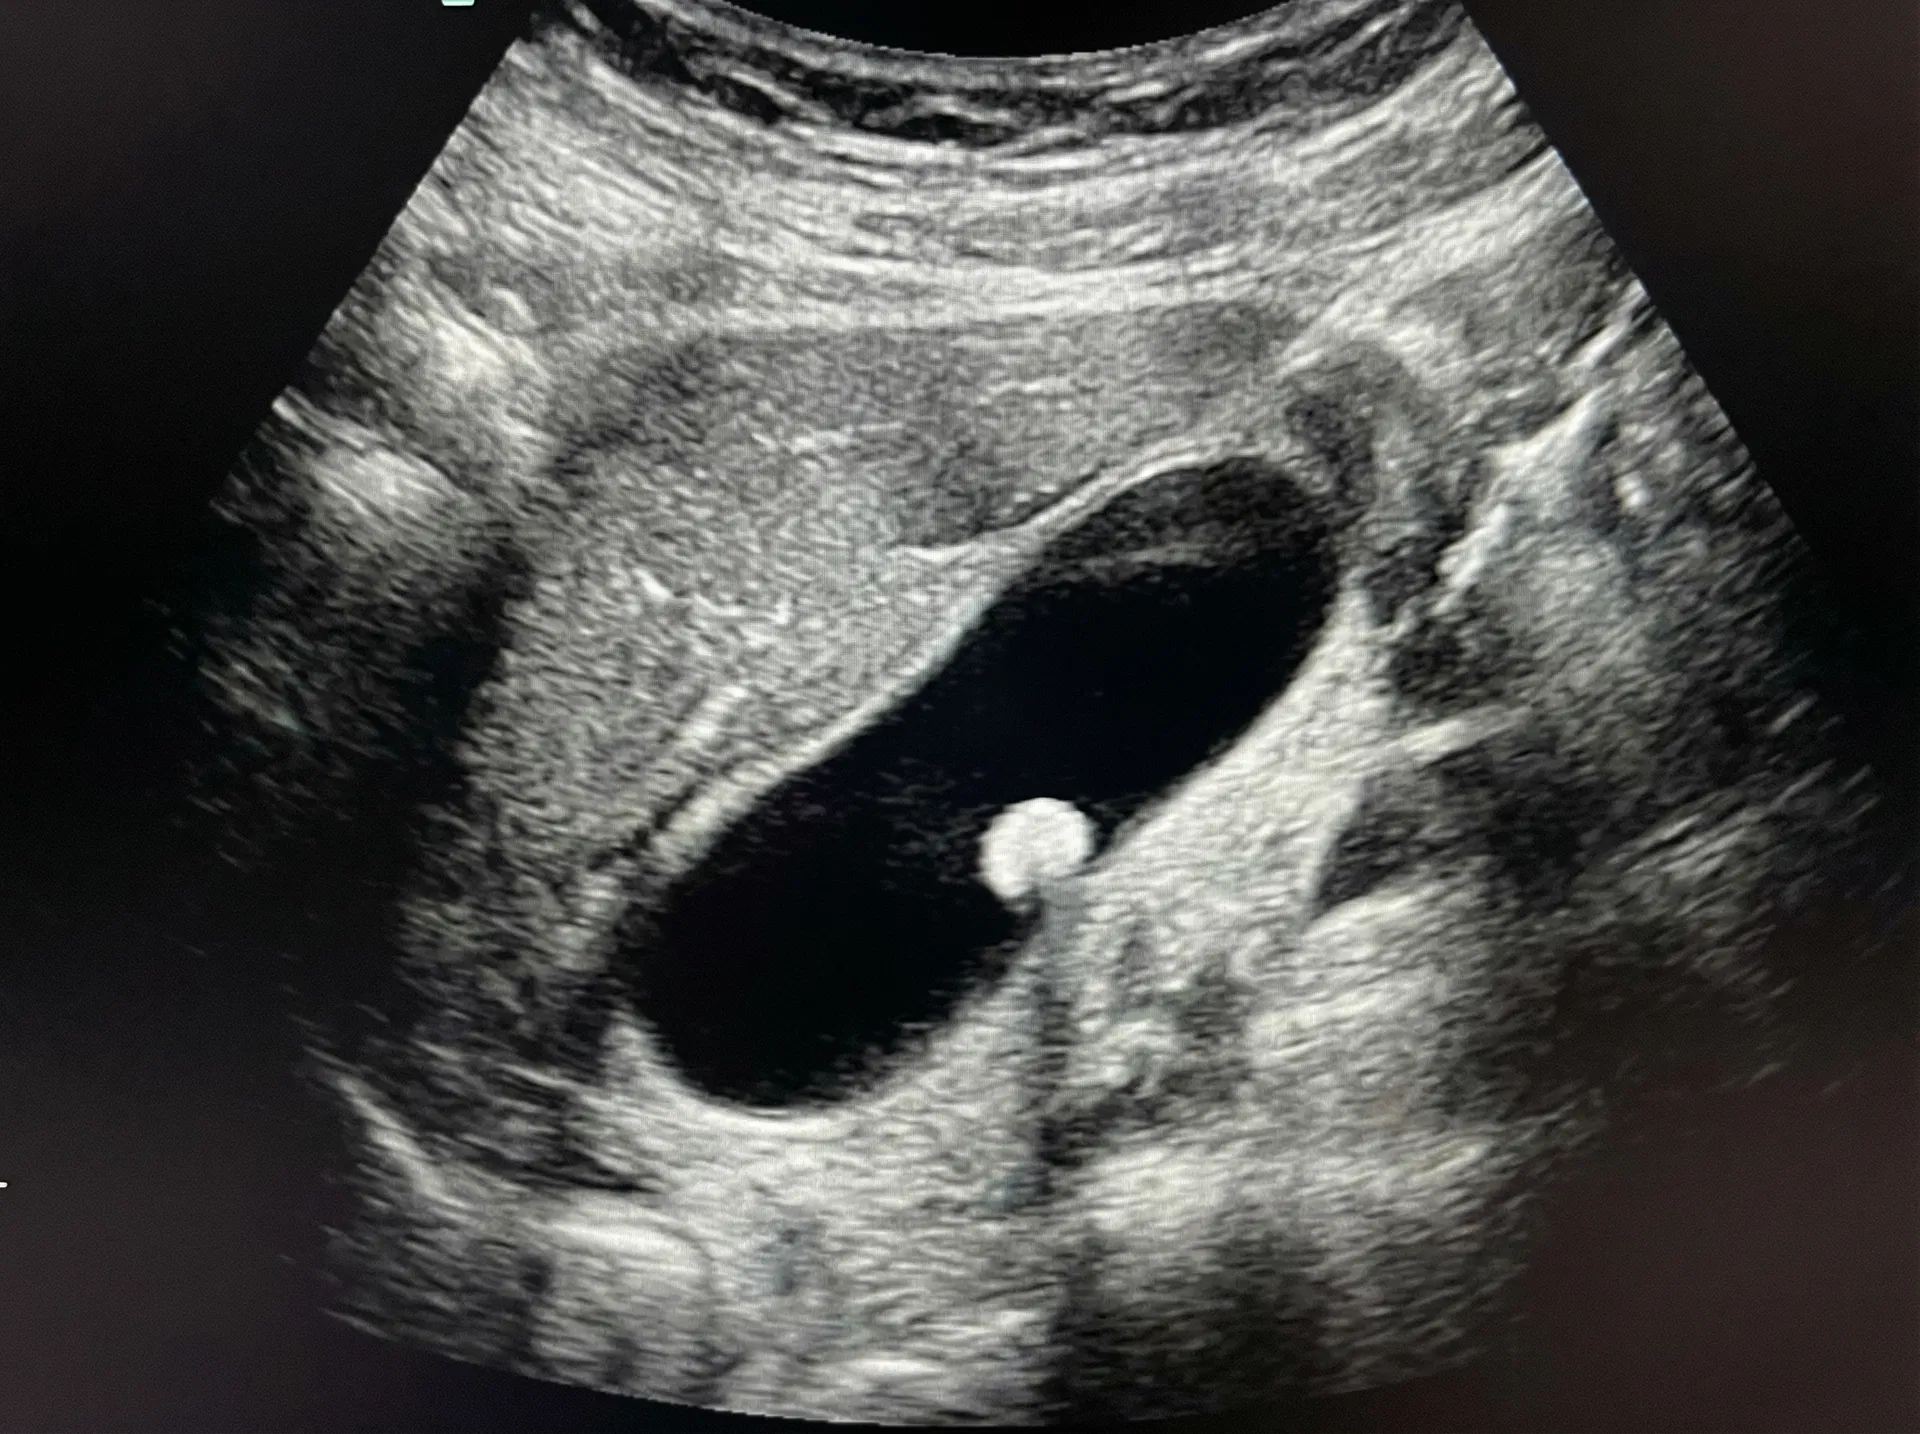

Ultrasound scan showing a gallbladder polyp — a small bright growth protruding from the inner wall of the gallbladder. This is how most gallbladder polyps are discovered during routine scans.